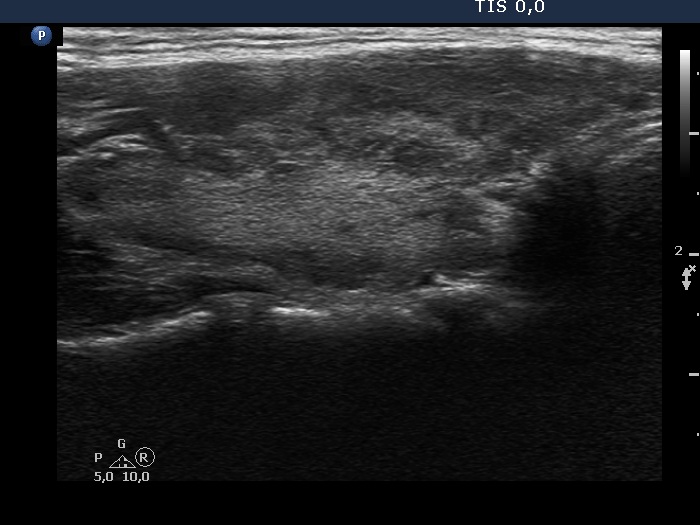

Right lobe, longitudinal scan